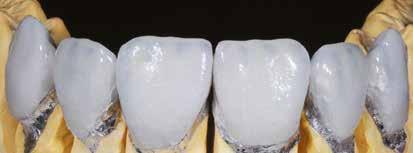

A cikkünkben bemutatásra kerülő eset ellátása során preparációt héjak készre vitele során a platinafólia technikát alkalmaztuk.

kívül vékonyak, és ezáltal a végleges rögzítésük előtt jelentős olyan minimál invazív kezelési eljárásnak számítanak, amely

elérni. A fent leírtak alapján bátran

preparációt nem igénylő héjak készítése mellett döntöttünk. A alkalmaztuk. Annak ellenére, hogy az elkészítésre kerülő héjak rendjelentős törésveszéllyel állunk szemben, összességében mégis amely segítségével kifogástalan esztétikai eredményeket lehet javasoljuk e módszer alkalmazását.

A fogászati kezelések során manapság már nem kizárólag az esztétikai megjelenés helyreállítására törekszünk. Sokszor a kedvezőtlen esztétikai megjelenés hátterében álló okok következményes módon a fogazat funkcionális működését is károsítják, így a kezelések során ezeknek a helyreállításával is foglalkoznunk kell. A különböző funkcionális és esztétikai diszkrepanciák kezelésére számtalan módszer létezik, ám ezen fogászati beavatkozások mindegyikében közös, hogy a kivitelezésük során nagyon szoros együttműködésre van szükség a kezelést végző fogorvos és a munkáját segítő fogtechnikus között. Az alábbi esetbemutatás során egy fiatal hölgypáciens fogazatának héjak alkalmazásával történő esztétikai és funkcionális rehabilitációját szeretnénk ismertetni.

Esetbemutatás

A 19 éves hölgypáciens azzal a kéréssel jelentkezett a rendelőnkbe, hogy szebb fogakat szeretne. Az első konzultáció alkalmával megkérdeztük, hogy mi zavarja leginkább a fogazatának jelenlegi megjelenésében, valamint azt is megbeszéltük vele, hogy milyen végeredmény elérése esetén lenne maradéktalanul elégedett. Ebben az esetben a kezelési célokat az alábbiakban határoztuk meg:

A páciens fogazata esztétikai megjelenésének és funkcionális működésének a lehető legtöbb, saját foganyag megtartása mellett történő helyreállítása (1. és 3. ábra). A lehető legideálisabb esztétikai végeredmény elérése érdekében néhány esetben a fogak alakjának módosítá -

sára is szükség van (2. és 4. ábra).